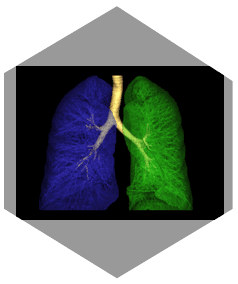

Großer Durchmesser für vielfältige Anwendungen

» 76 cm Scanbereich/

250 kg Tischkapazität und 21 Lp/cm Auflösung sind problemlos möglich

» Bequeme Positionierung von adipösen Patienten ohne

Kompromisse bei Dosis oder Bildqualität.